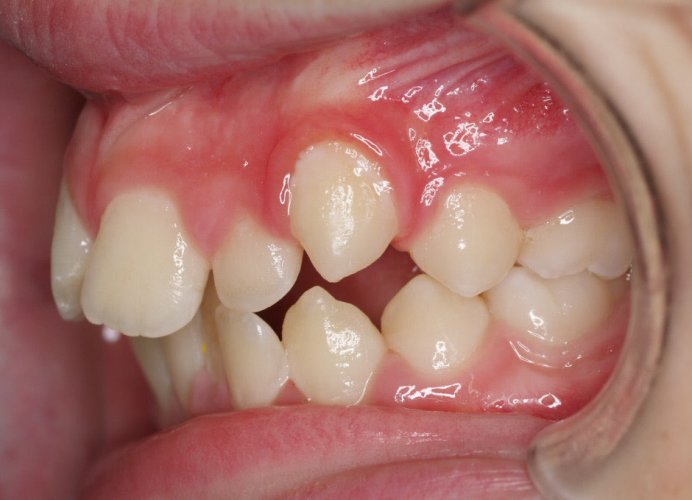

Un “diastema” es una separación extraordinariamente grande entre dos o más dientes. La mayoría de las veces, el diastema aparece entre los dos dientes delanteros superiores. Muchos niños tienen diastema cuando se les caen los dientes de leche, pero en la mayoría de los casos esta distancia desaparece cuando salen los dientes permanentes.

Los diastemas pueden deberse a una diferencia en los tamaños de los dientes, a la falta de algún diente o a que el frenillo labial sea demasiado grande. El frenillo labial es el tejido que va desde el interior del labio hasta la encía, en el lugar donde se sitúan los dos dientes delanteros superiores. Los diastemas también pueden deberse a problemas en la alineación de la boca, como la sobremordida horizontal o la protrusión de los dientes1.